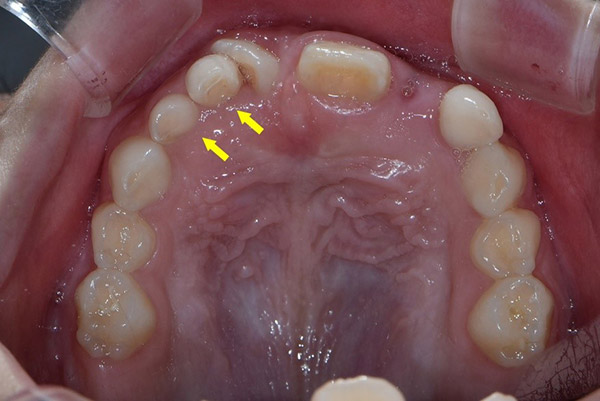

유치 20개, 영구치 32개 외에 추가 치아가 존재하는 것을 '과잉치'라고 한다./사진=서울대치과병원 제공

사람은 평생 52개(유치 20개, 영구치 32개)의 치아를 가지고 살아간다. 그러나 간혹 이 외에 추가 치아가 자라나는 경우가 있는데, 이것이 '과잉치'다. 과잉치가 발생하는 정확한 원인은 아직 밝혀지지 않았다. 전문가들은 치아가 발육하는 과정에서 치아가 만들어지는 '상피조직'이 과하게 활성화하는 것을 원인으로 추측한다. 부모·형제가 과잉치를 가지고 있었다면 자녀나 다른 형제에게도 발생할 가능성이 높다. 유치보다는 영구치에서 발생하는 빈도가 높으며 주로 위턱 대문니(앞니의 가운데 위·아래로 두 개씩 있는 넓적한 이) 근처에서 원뿔 형태로 나타난다.